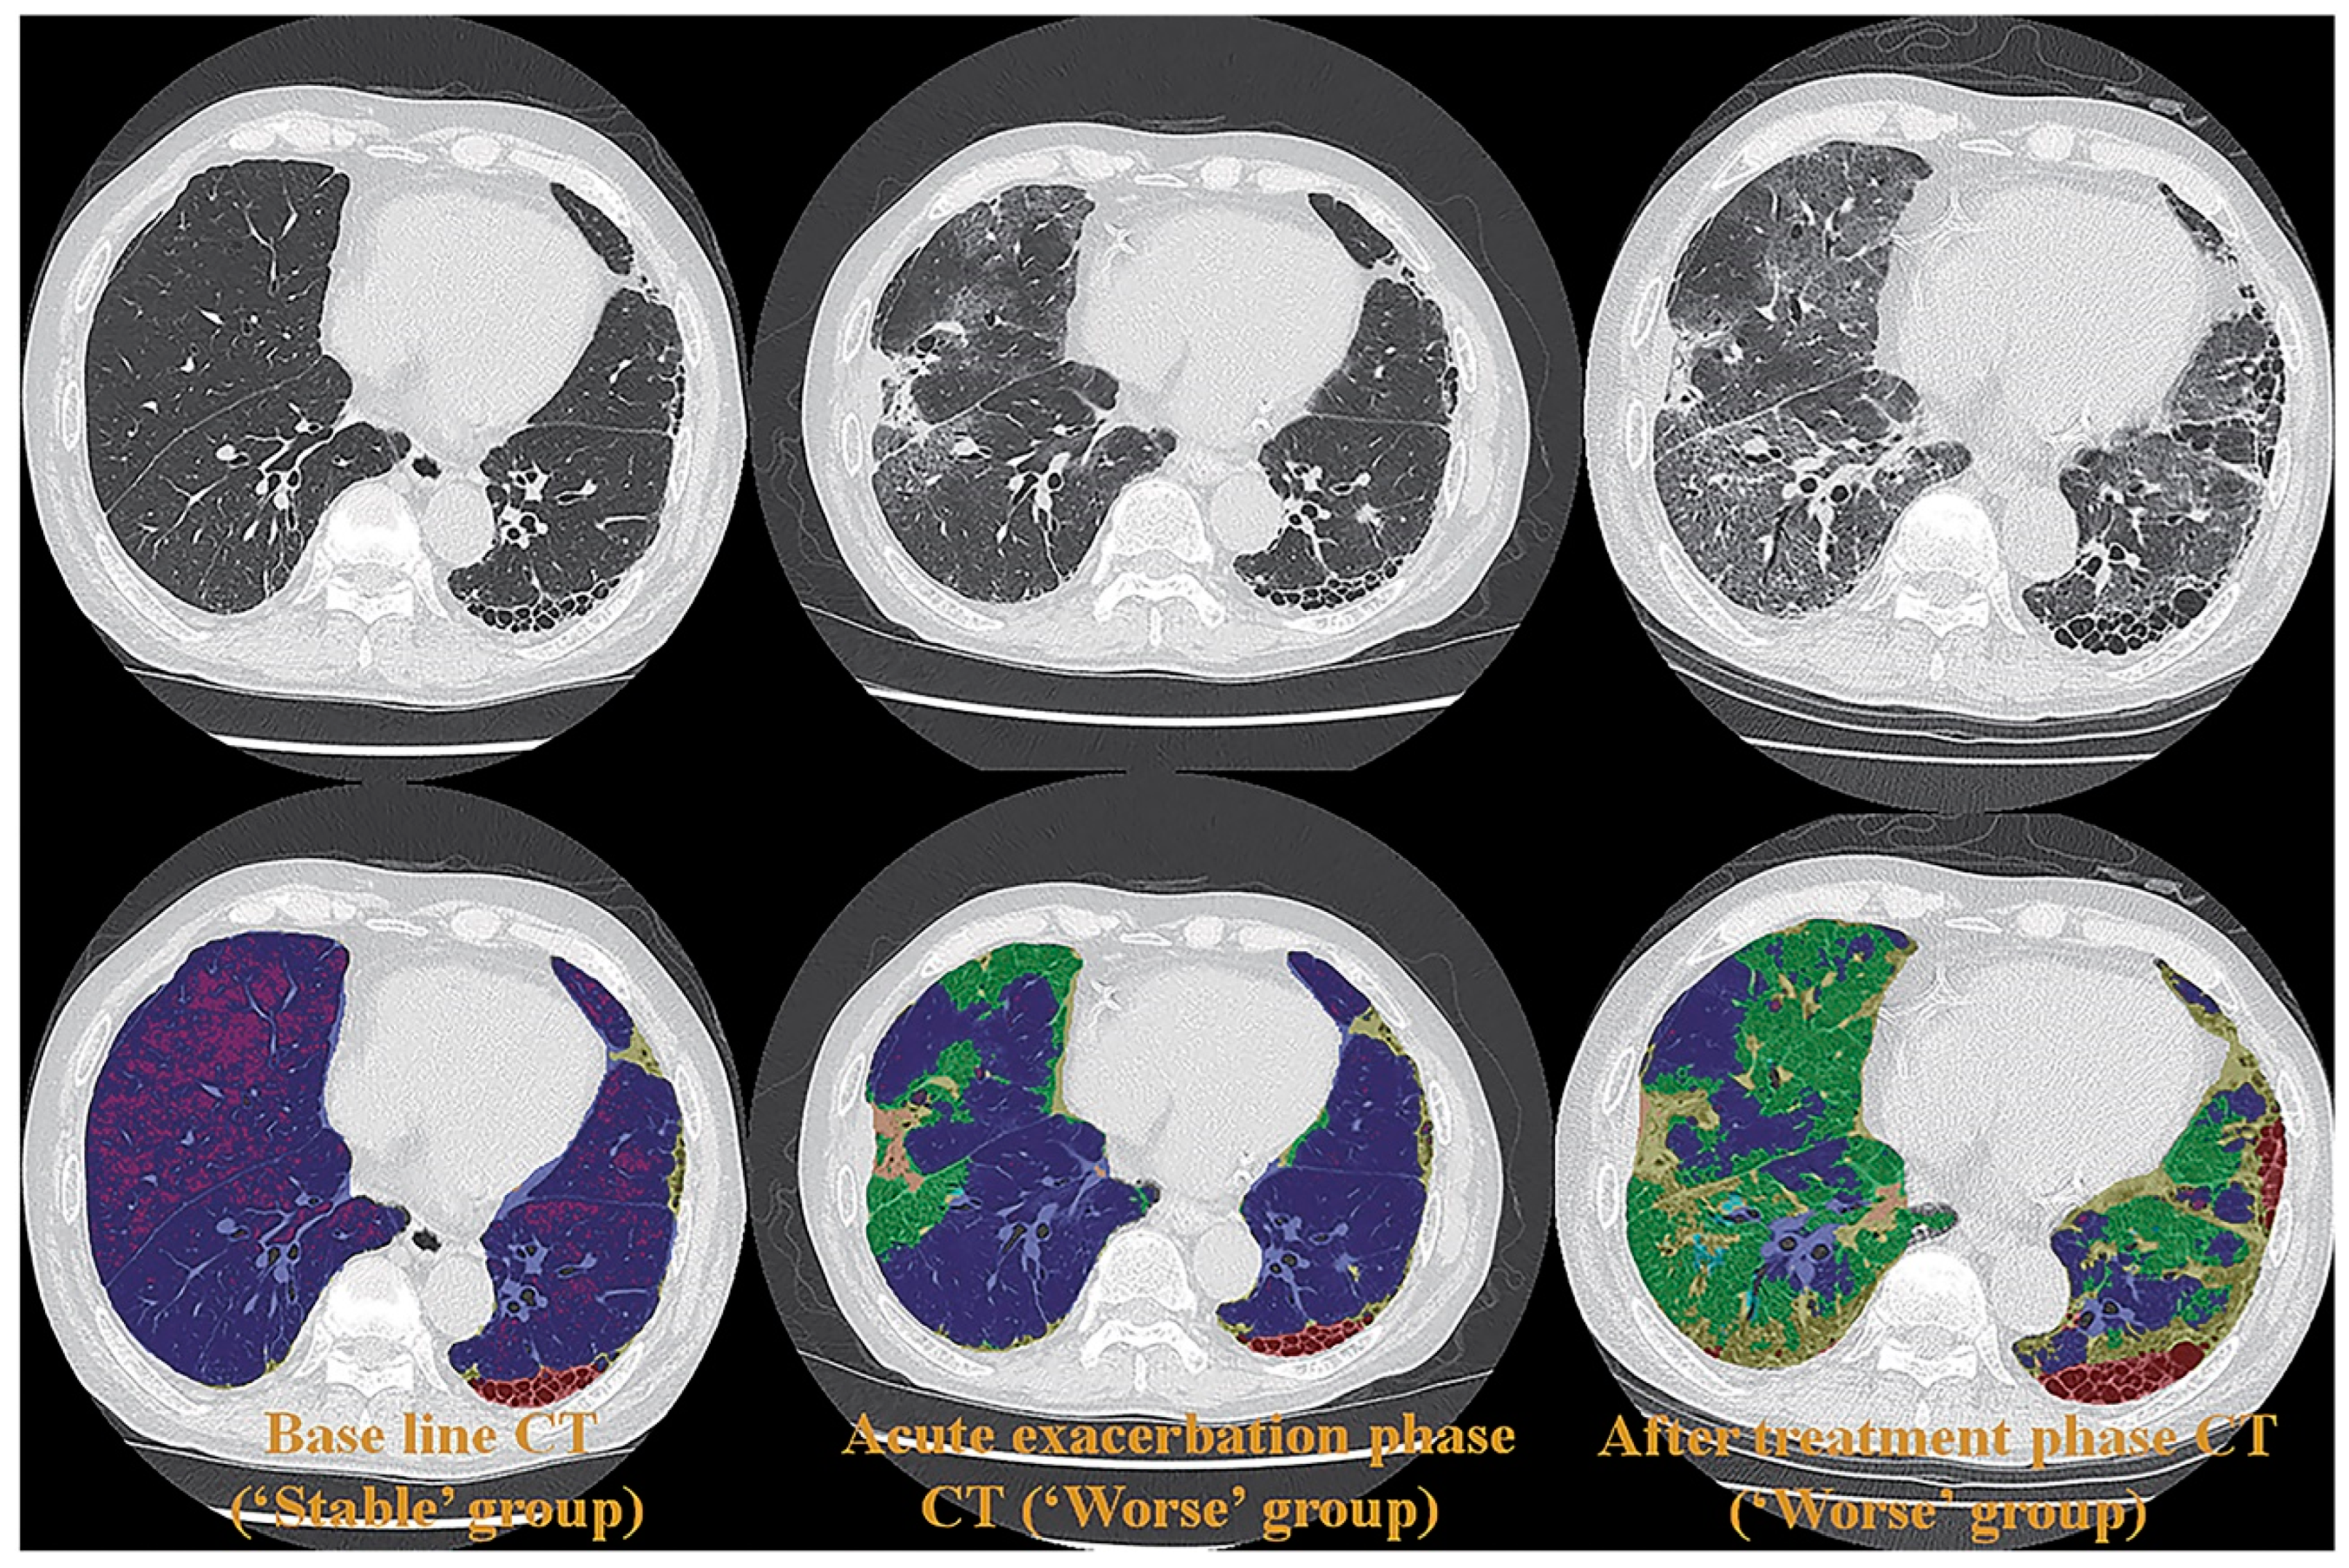

- Ohno, Y.; Aoyagi, K.; Arakita, K.; Doi, Y.; Kondo, M.; Banno, S.; Kasahara, K.; Ogawa, T.; Kato, H.; Hase, R.; et al. Newly developed artificial intelligence algorithm for COVID-19 pneumonia: Utility of quantitative CT texture analysis for prediction of favipiravir treatment effect. Jpn. J. Radiol. 2022, 40, 800–813. [Google Scholar] [CrossRef] [PubMed]

- Ohno, Y.; Aoyagi, K.; Takenaka, D.; Yoshikawa, T.; Fujisawa, Y.; Sugihara, N.; Hamabuchi, N.; Hanamatsu, S.; Obama, Y.; Ueda, T.; et al. Machine learning for lung texture analysis on thin-section CT: Capability for assessments of disease severity and therapeutic effect for connective tissue disease patients in comparison with expert panel evaluations. Acta Radiol. 2022, 63, 1363–1373. [Google Scholar] [CrossRef]